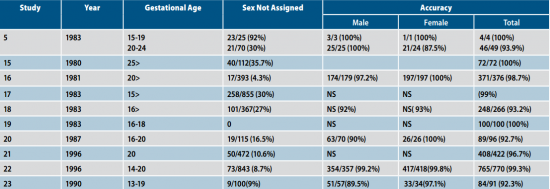

קביעת מין העובר בטרימסטר השני

בניגוד לקביעת המין בטרימסטר הראשון, קביעת המין בטרימסטר השני מבוססת על הדגמה ישירה של איברי המין: שק האשכים והפין אצל זכרים והשפתיים אצל נקבות. טבלה 2 מראה שהדיוק בקביעת מין העובר בטרימסטר השני נע בין 92 אחוז ל-100 אחוז[5][15][16][17][18][19][20][21][22][23]. בחלק מעבודות אלו, הדיוק בקביעת המין היה יותר גדול בנקבות[20][23] ובחלקן בזכרים[5][16]. עבודתו של Natsuyama[6] אינה מופיעה בטבלה 2 מאחר שהוא השתמש בקריטריונים אחרים לקביעת המין כגון מדידת המרחק ה-anogenita והזווית ה-ischiogenita והצליח לאבחן מין העובר ב-99.9 אחוז מהעוברים, אך מדדים אלה לא דווחו בעבודות אחרות.